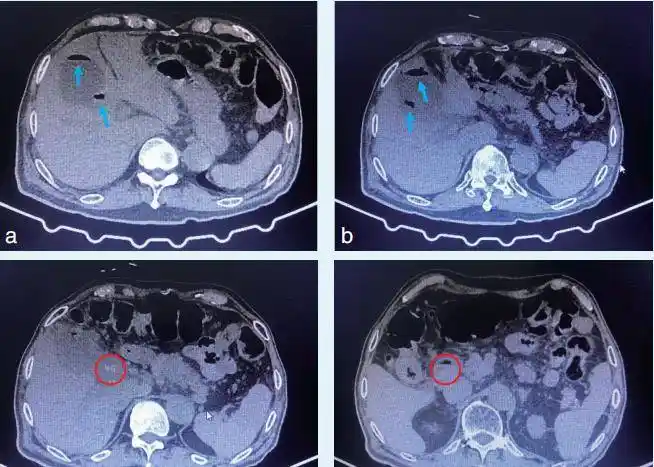

疑难"镜"解 - 胆道子母镜诊治胆囊颈部结石1例_检查_患者_治疗